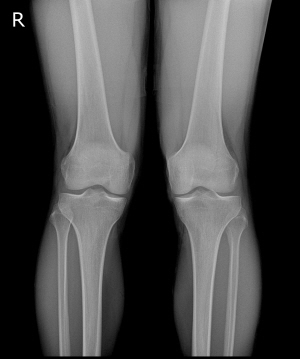

22세 퇴행성 관절염 환자 엑스레이 사진​./사진=연세사랑병원 제공

퇴행성관절염은 주로 장년층에 나타나는 탓에 '노화로 인한 질병'으로 알려졌지만 반드시 그런 것만은 아니다. 중년층은 물론, 20~30대에도 관절염을 겪는 경우가 있고 그 원인이 유전인 경우가 적지 않다.

문제는 퇴행성관절염이 통증뿐 아니라 '휜 다리'를 유발할 수 있다는 것. 보건복지부 지정 관절전문 연세사랑병원 고용곤 병원장은​ "휜 다리는 무릎 관절 각도가 표준 범위를 넘어선 상태를 뜻한다"며 "유전적인 요인에 의해 발생하는 경우가 더러 있기 때문에 늦지 않게 병원을 방문하는 것이 중요하다"고 말했다.